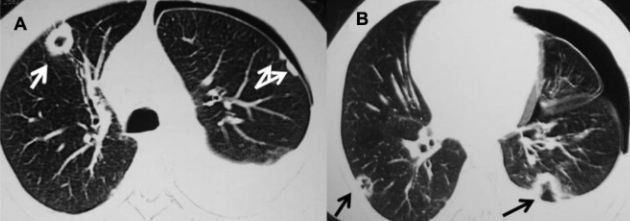

CT

- Nodules nécrobiotiques avec cavitations et prédominance sous-pleurale

- Plutot petits-moyens en taille (contrairement DD: Wegener)

- Complications: Pneumothorax